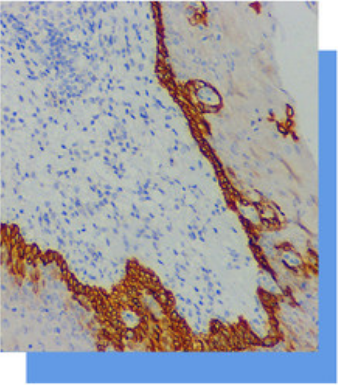

CK14是一种分子量为50kD的细胞角蛋白。在

肌上皮以及基底细胞CK14+。其主要应用于

鳞状细胞癌(尤其是低分化) (92%+) 与

腺癌(7%+)的鉴别诊断。在甲状旁腺中,嗜酸

性腺瘤阳性率为92%,嗜酸性癌为阴性表达。